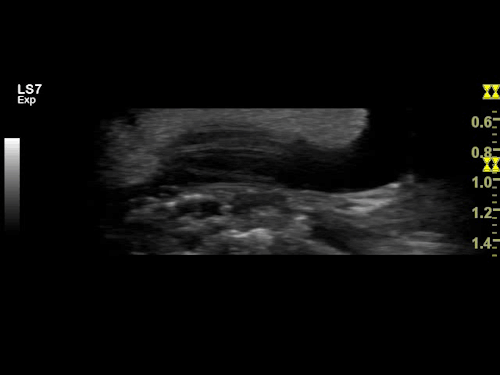

Quit Wriggling: Fifi’s ultrasound.

Fiona Mildren, an imaging and ultrasound manager at GE Healthcare Systems, has been on hand to help administer the technology even though she an ophidiophobe – afraid of snakes – herself. “It was really interesting to see that snake ovaries look a lot like human ovaries in an ultrasound,” Mildren says. “In fact, sometimes while I was doing the ultrasound I’d even forget that she was a snake – until she wriggled, that is.”

Fifi was caged with a male death adder over the hottest part of summer, and Mildren was delighted to see the tiny flicker of baby-snake heartbeats when she got scanned a few months later.

“We’re amazed by how much we can see thanks to this ultrasound technology,” Staples says. “This is the first time we’ve been able to know with 100 percent certainty that a snake is pregnant, and that has given us the opportunity to prepare for the birth well in advance.”